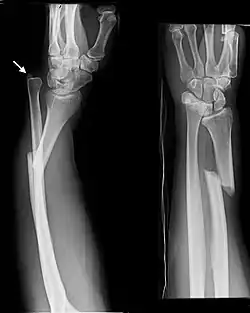

Galeazzi fracture

| Galeazzi fracture-dislocation | |

| Galeazzi fracture. Arrow points at the dislocated ulnar head | |

The Galeazzi fracture is a fracture of the distal third of the radius with dislocation of the distal radioulnar joint. It classically involves an isolated fracture of the junction of the distal third and middle third of the radius with associated subluxation or dislocation of the distal radio-ulnar joint; the injury disrupts the forearm axis joint.[1]

Galeazzi fractures are best treated with open reduction of the radius and the distal radio-ulnar joint.[3] It has been called the "fracture of necessity," because it necessitates open surgical treatment in the adult.[4] Nonsurgical treatment results in persistent or recurrent dislocations of the distal ulna.[1] However, in skeletally immature patients such as children, the fracture is typically treated with closed reduction.[1]